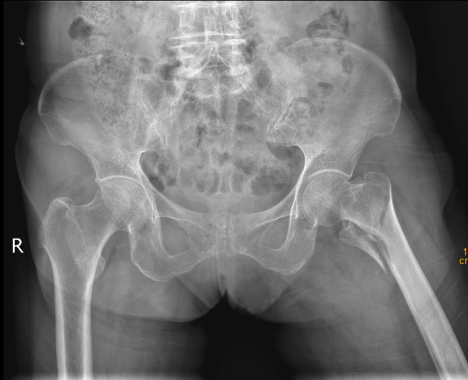

93 岁 的患者李奶奶和 91 岁 的患者蒋奶奶,都是在家不慎摔跤,急诊检查后发现为 股骨粗隆间骨折,进而入住我院骨科接受治疗。

我院多科室协同合作, 根据快速康复理念,经详细检查、排除禁忌症、与家属充分沟通后,成功为李奶奶、蒋奶奶实施 股骨粗隆间骨折闭合复位内固定术(PFNA),手术治疗效果良好。

髋部骨折,又称为股骨近端骨折,常见的是股骨粗隆间骨折、股骨颈骨折。